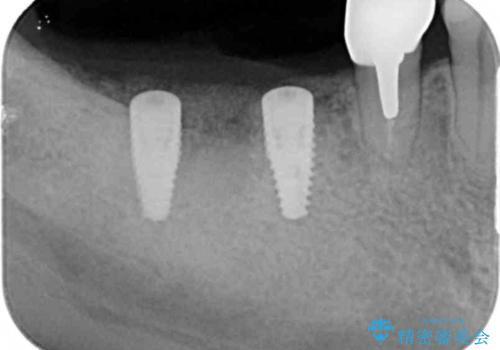

ブリッジを支える歯が割れてしまい、抜歯が必要であることと、骨の大きな吸収が見られました。

インプラント治療を行うにあたり周囲に骨を造成することで安定して噛める環境の整備を計画します。

今回はインプラント埋入時に固定が得られたので同時に骨の造成を行い治療を進めることができました。